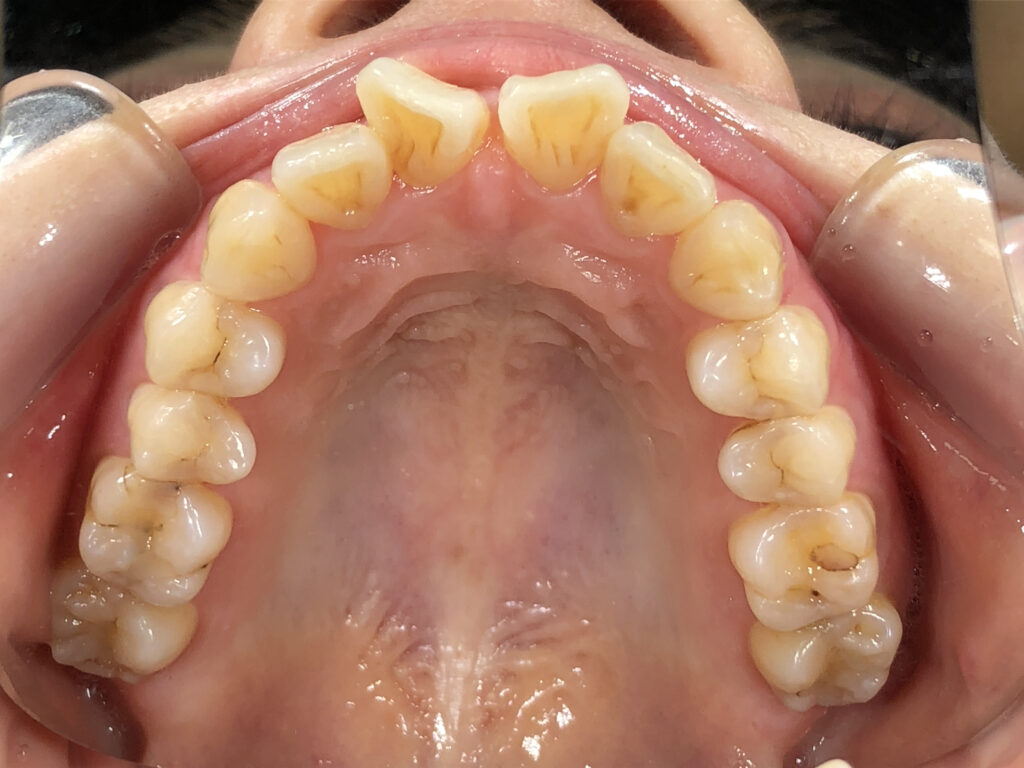

上顎

治療前